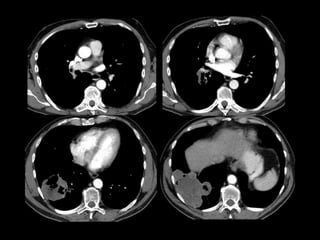

Mujer de 18 años con episodio de hemoptisis con

exploración ORL normal

Mujer de 18años con episodio de hemoptisis con exploración ORL normal